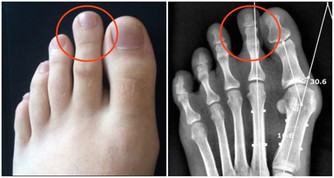

9. 眼球突出

格雷夫斯病是一種甲狀腺疾病,因為甲狀腺機能亢進,

患者的通常會出現眼球突出的症狀,新陳代謝的速度也會加快,還有可能會引起甲狀腺腫大。